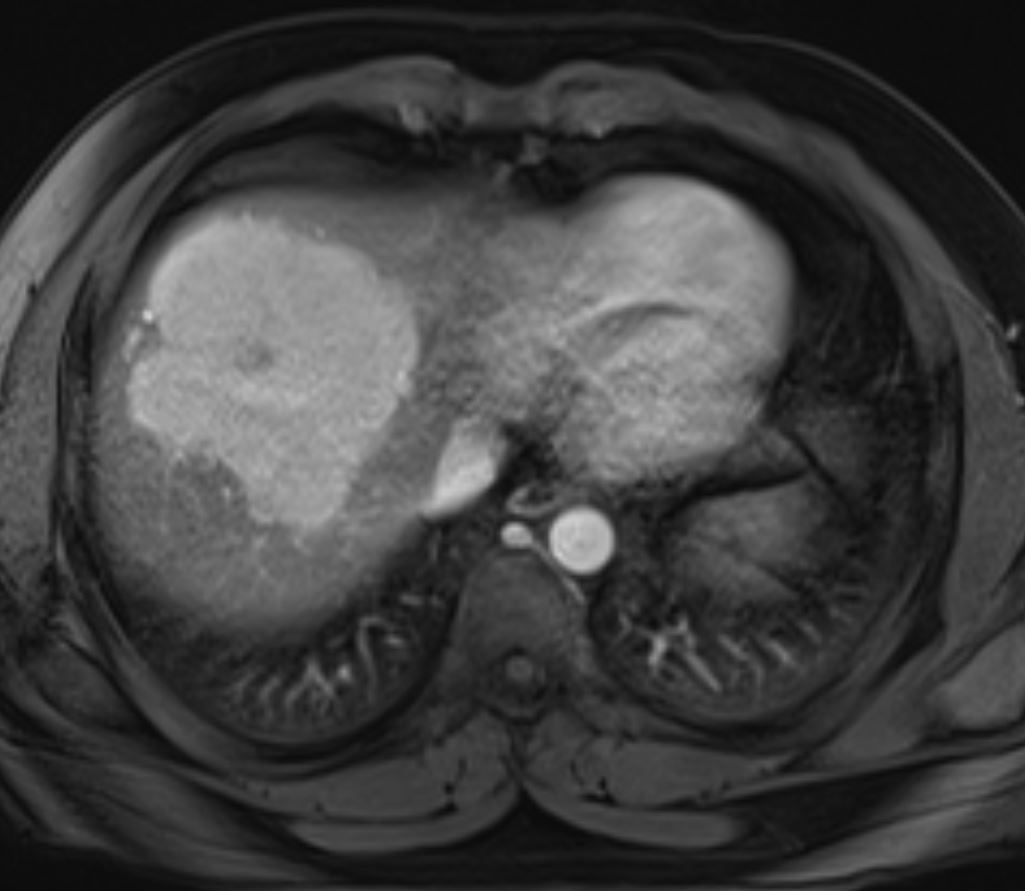

Young man presents with abnormal ultrasound and elevated liver function tests. What is the most likely diagnosis?

What is your diagnosis?